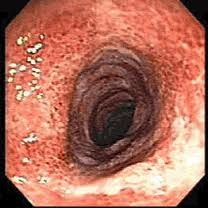

- Colonoscopía diagnóstica y terapéutica (con sedación)

- La colonoscopía es un método seguro y eficaz de examinar el interior del colon y el recto, para lo cual se utiliza un instrumento tubular flexible. Se usa para diagnosticar problemas del colon y recto, y para realizar biopsias y extirpar pólipos de colon. La mayoría de las colonoscopías se realizan de forman ambulatoria con el mínimo de inconvenientes y molestias.